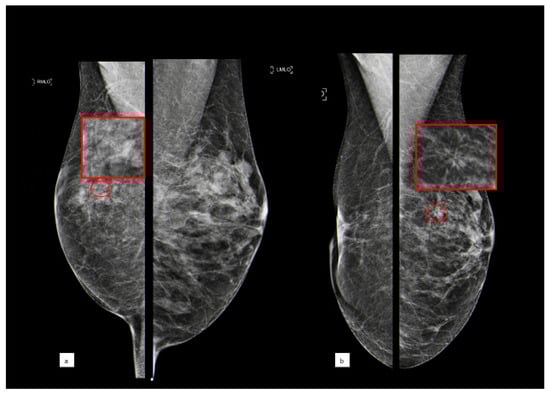

Figure 2 shows the case of a B3 lesion in the right breast of a patient who developed an invasive breast cancer in the contralateral breast after 5 years.

Figure 2.

A 56-year-old patient with a cluster of microcalcifications at the upper outer quadrant of the right breast that was diagnosed as ADH after biopsy ((a) MLO bilateral view, with the red circle showing microcalcifications corresponding to a B3 lesion; the red square shows a magnification of this area); the woman underwent surgical excision and after five years developed an architectural distortion in the contralateral breast ((b) MLO bilateral view, with the red circle showing distortion; the red square shows a magnification of this area) that, after biopsy, turned out to be invasive ductal carcinoma.